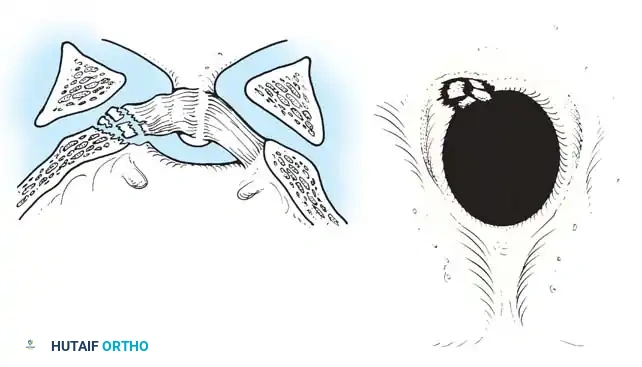

Fig 1. Important anterior and posterior supporting structures of the cervical spine. Understanding the integrity of the anterior longitudinal ligament, annulus fibrosus, and posterior ligamentous complex is paramount.

* Stage 1: Failure of the PLC, evidenced by facet subluxation in flexion and abnormal divergence of the spinous processes (widened interspinous distance).

* Stage 2: Unilateral facet dislocation. Subluxation of the contralateral facet suggests severe ligamentous injury. Beatson's serial sectioning studies demonstrated that unilateral dislocation can occur with rupture of only the posterior interspinous ligament and the facet capsule.

1. Exposure: Retract the longus colli muscles laterally to expose the anterior vertebral bodies and the damaged disc space.

2. Discectomy: Perform a complete discectomy using curettes and pituitary rongeurs. In trauma, the PLL is often torn; carefully remove any extruded disc fragments compressing the cord.

1. Open Reduction: If a facet is dislocated, carefully lever the inferior articular process of the superior vertebra over the superior articular process of the inferior vertebra using a Penfield elevator.